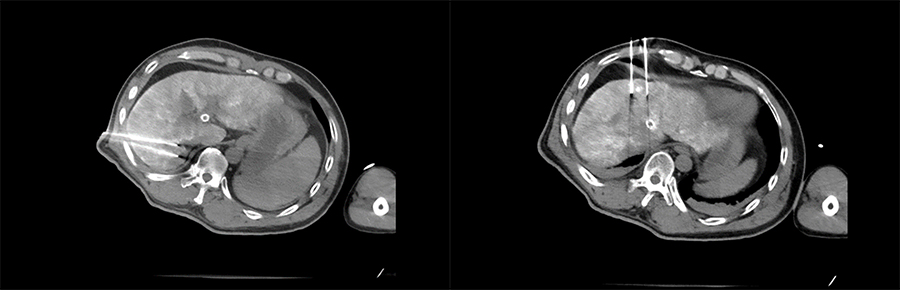

▲ 患者一术前影像

▲ 患者二术前影像

前影像